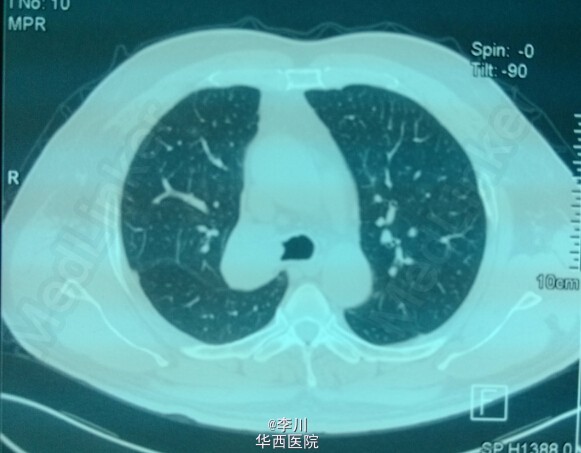

大医院技术更好?---右上肺鳞癌伴肺不张一例

患者为50岁男性,因咳嗽咳痰、痰中带血3+月入院。3+月前患者因上述症状于当地医院就诊,行相关检查后诊断为右肺上叶鳞癌。却被告知不能手术,只能放化疗。患者不甘心,遂于我院就诊,经我院知名专家详细读片评估后,认为有手术指证,首选手术治疗。查体心腹无特殊异常。右上肺呼吸音弱,未闻及干湿罗音,左肺呼吸音无明显异常。